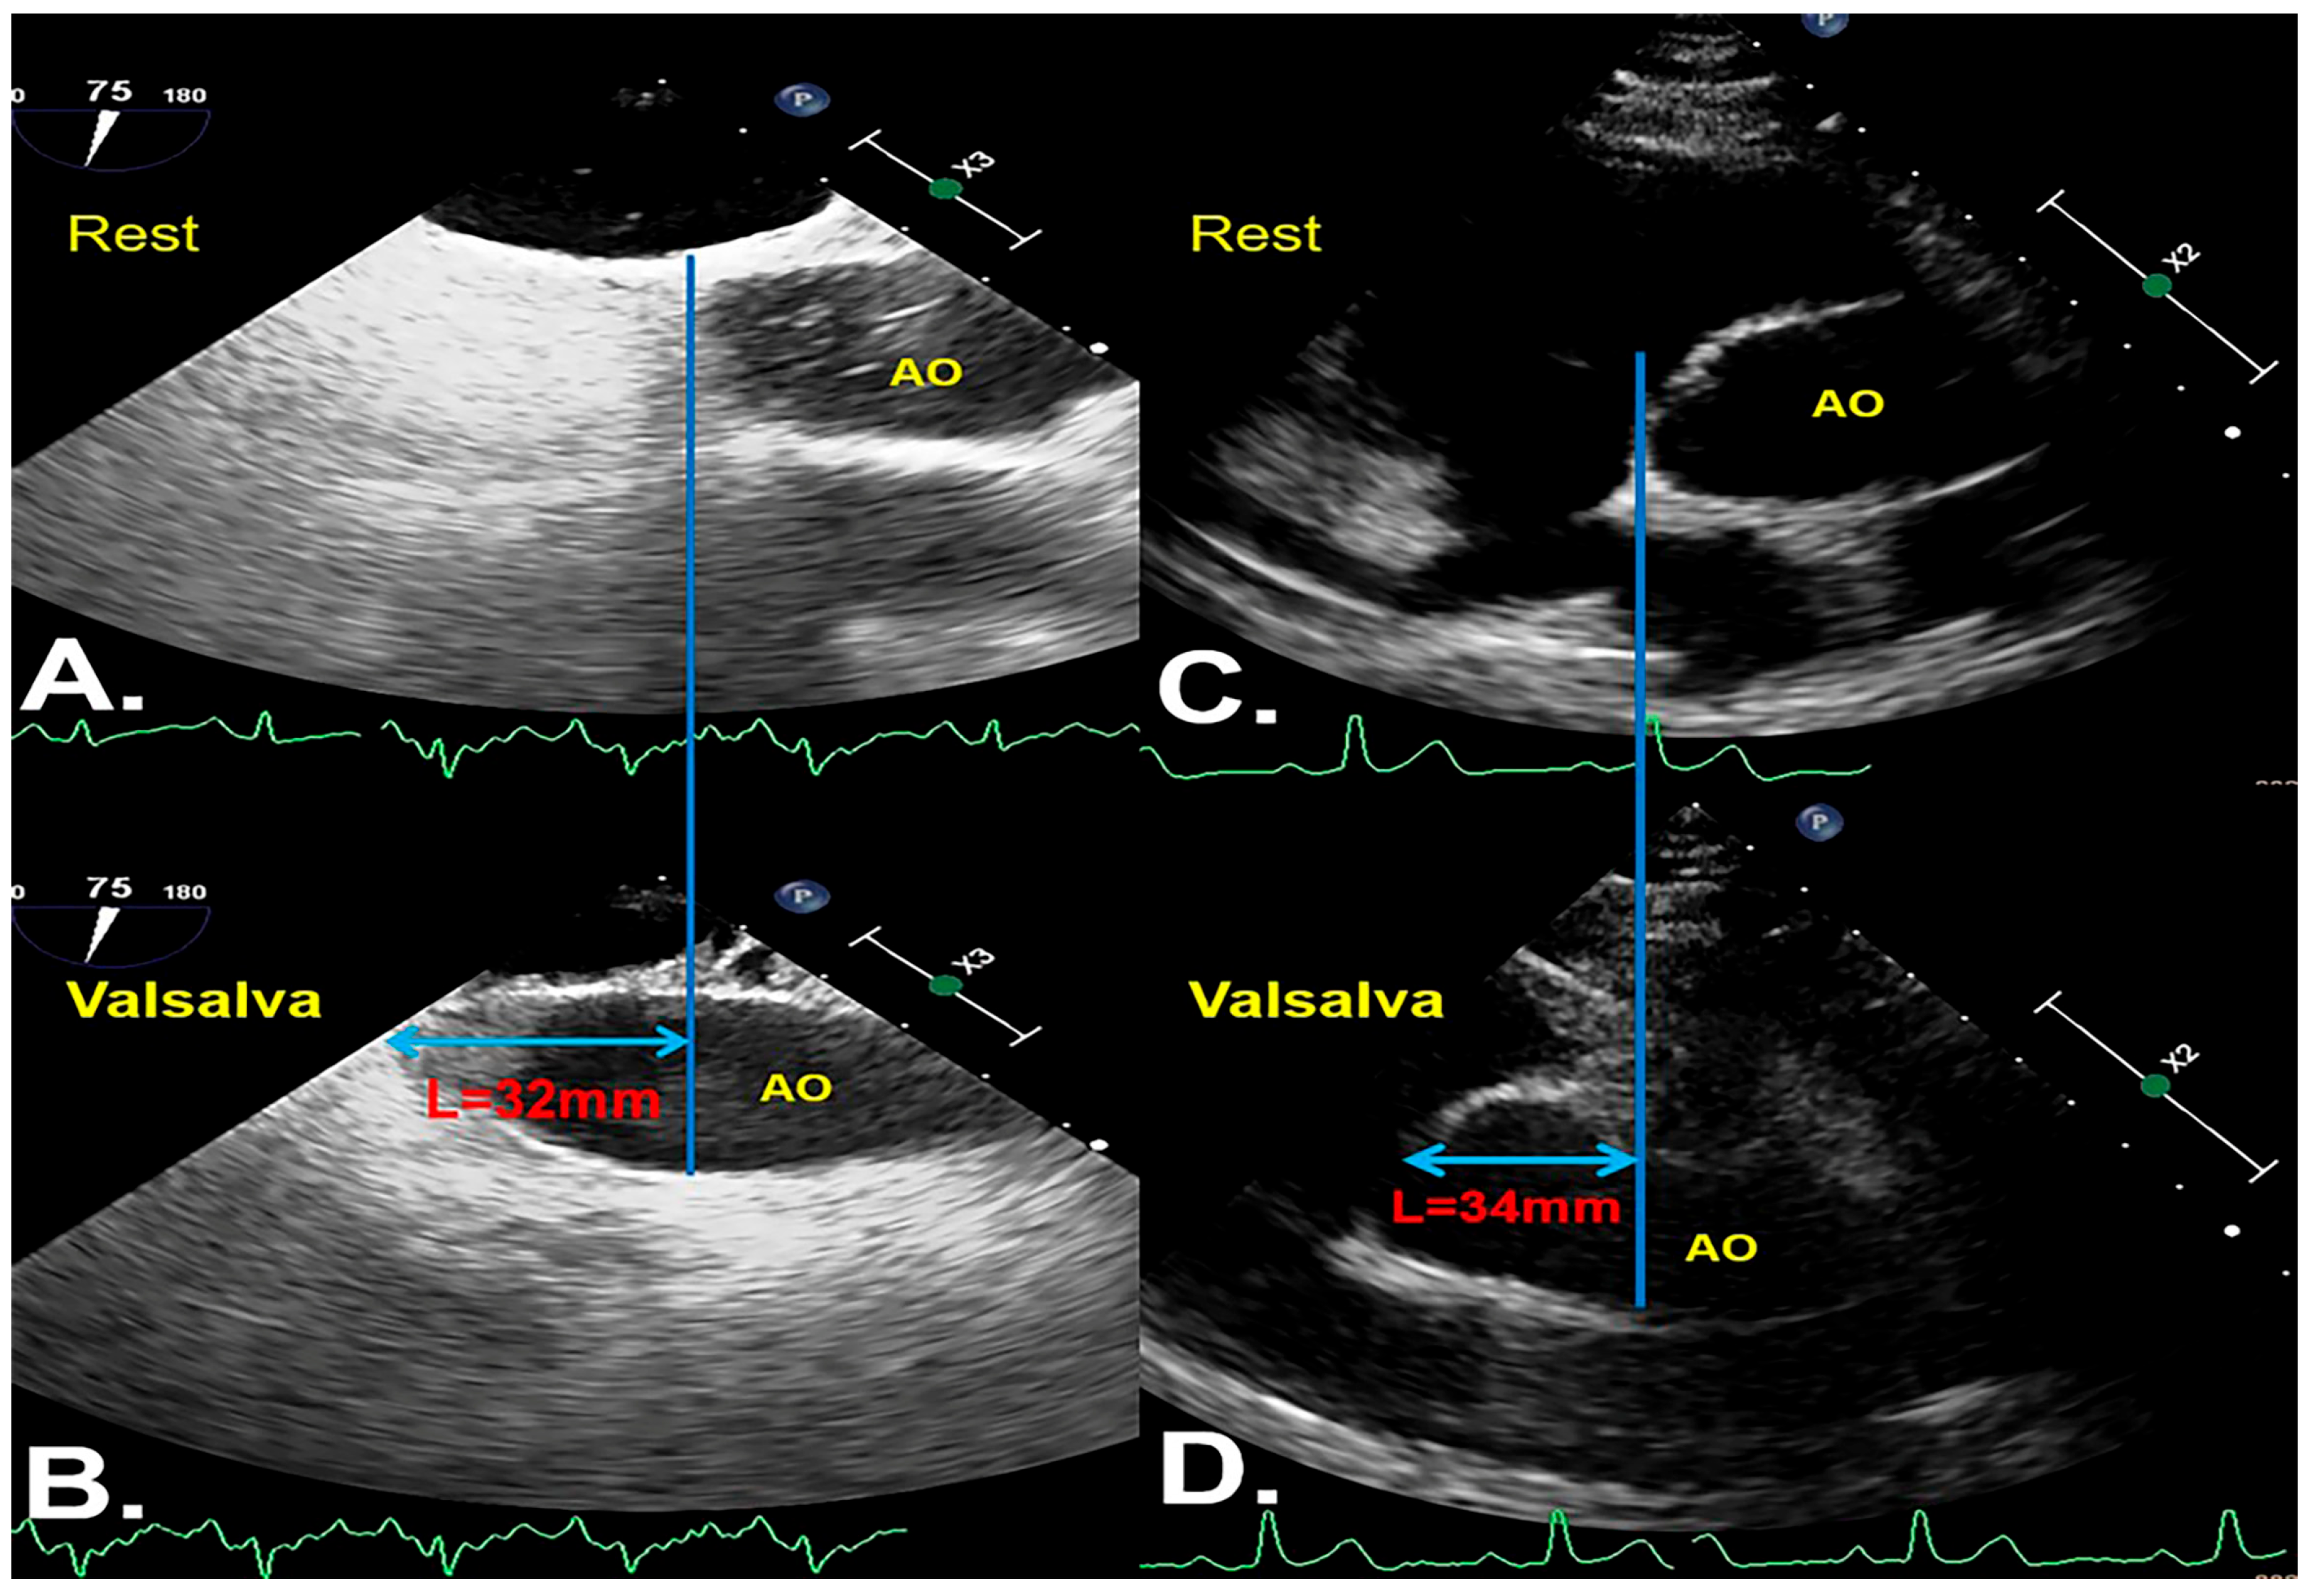

Aortic Root Downward Movement as a Novel Method for Identification of an Adequately Performed Valsalva Maneuver to Detect Patent Foramen Ovale during Transesophageal Echocardiography

2.2. Definitions